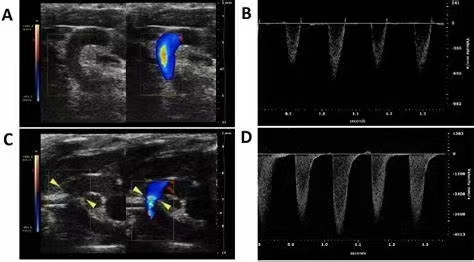

本周模型之— 主动脉弓缩窄模型